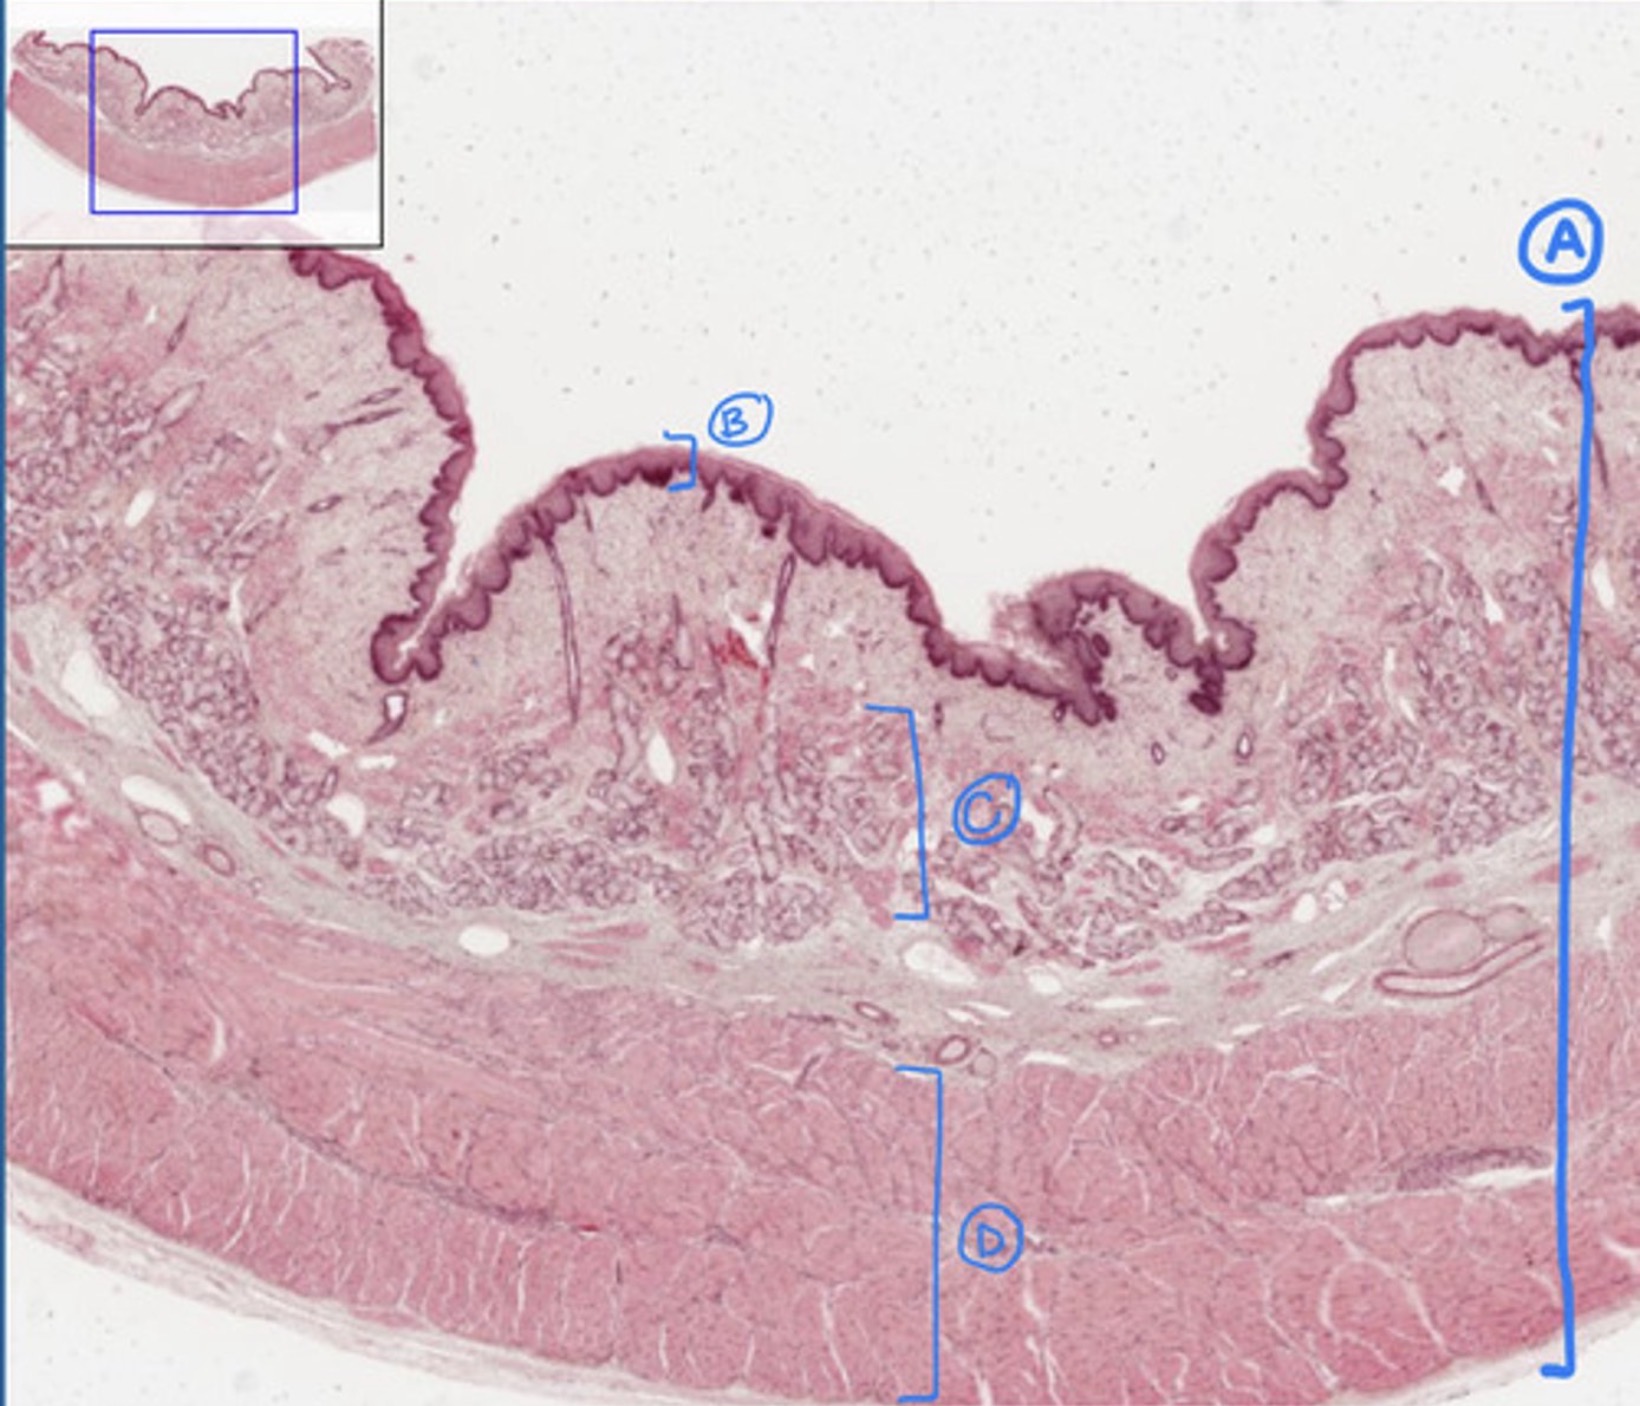

esophagus

A

mucosa of the esophagus

B

submucosa of the esophagus

C

muscularis of the esophagus

D